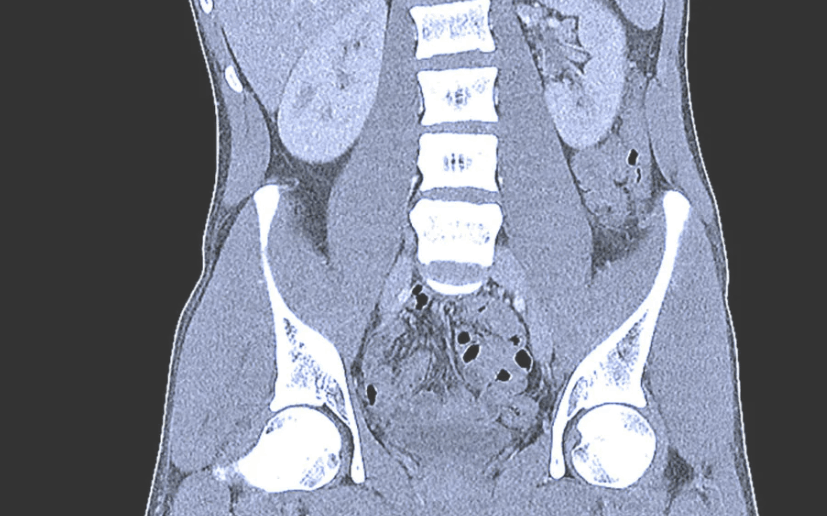

Brain CT scans can provide more detailed information about brain tissue and brain structures than standard X-rays of the head, thus providing more data related to injuries and/or diseases of t...